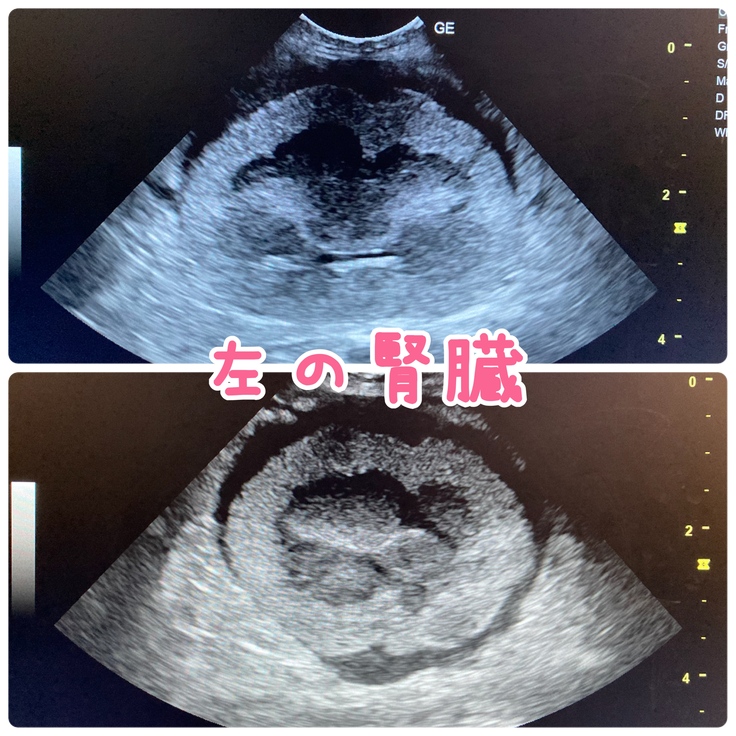

1/6に経過観察で受診をし、血液検査とエコー検査したところ

リンパ腫が転移した腎臓の状態は1週間前よりも悪くなっていました。

もしかしたら、腎臓以外の臓器にも転移している可能性が考えられると担当獣医に言われました。